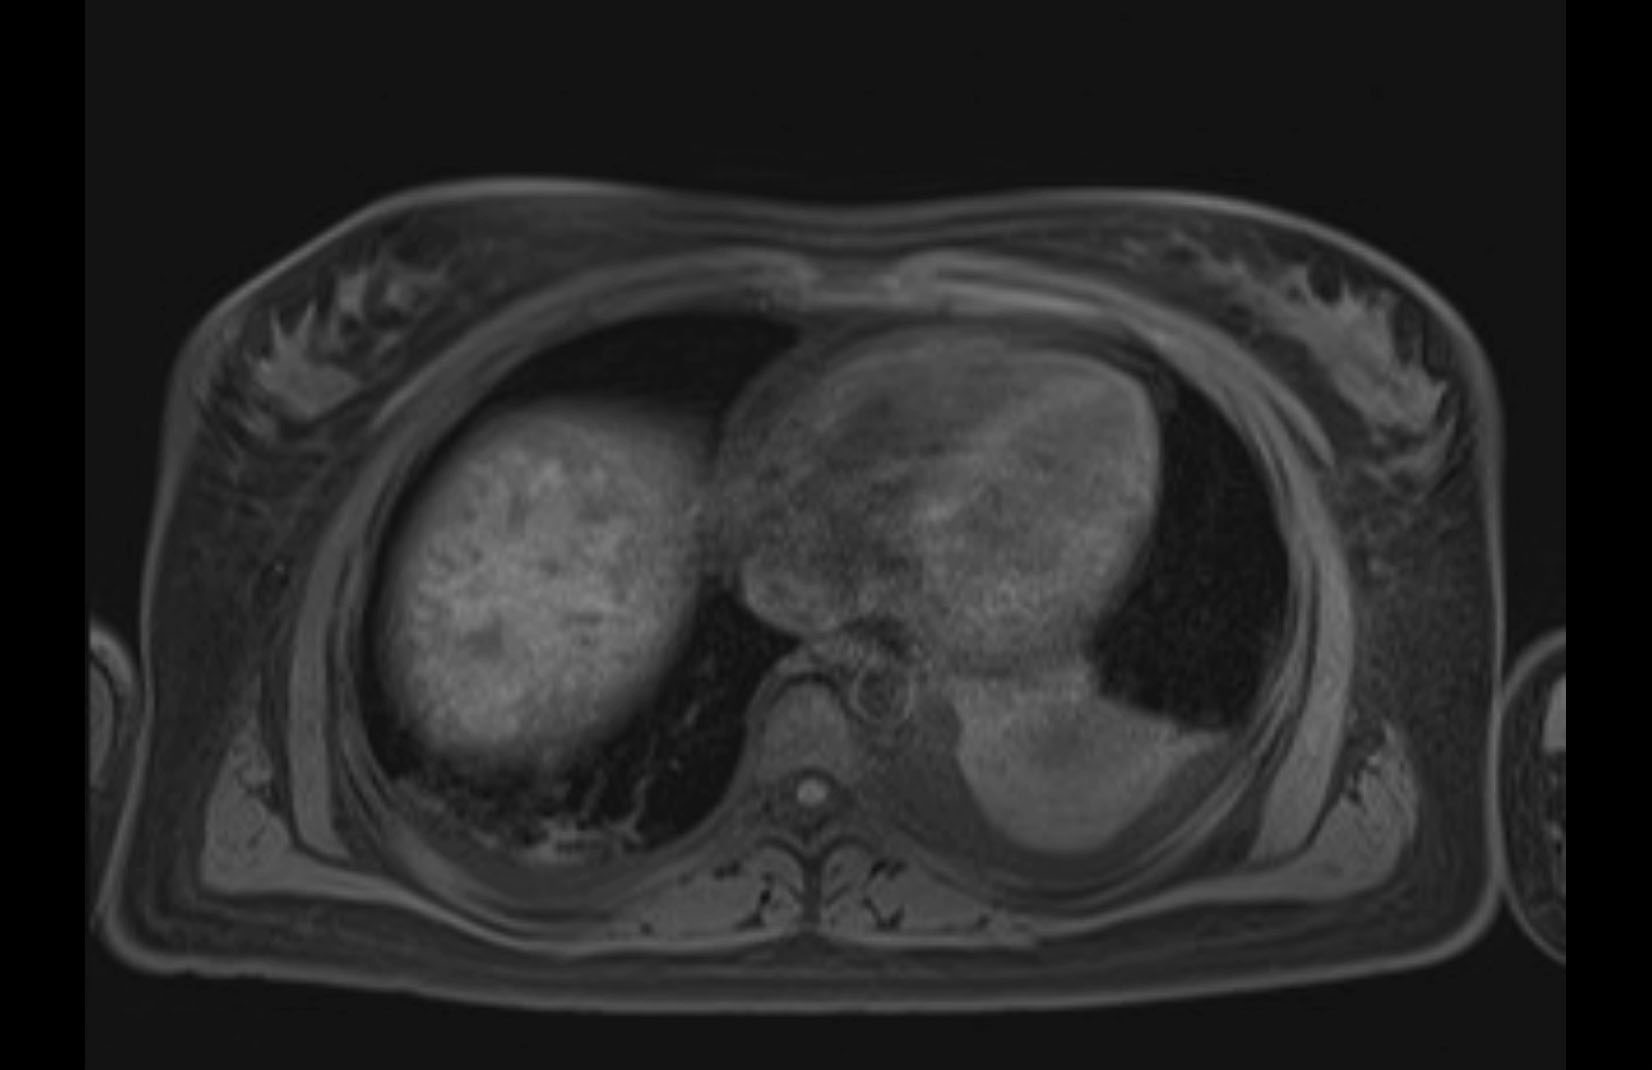

Imaging Analysis

Look through the patient's CT scan to identify any areas of concern for the necessary procedure.

MRI T2

Based on initial findings, which issue(s) would you be most concerned about?